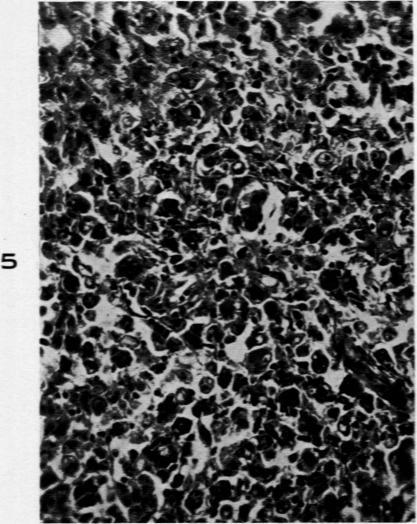

The Relation of Hodgkin's Disease, Lymphosarcoma and Reticulum Cell Sarcoma.

Am J Pathol. 1945 Mar;21(2):233-53.